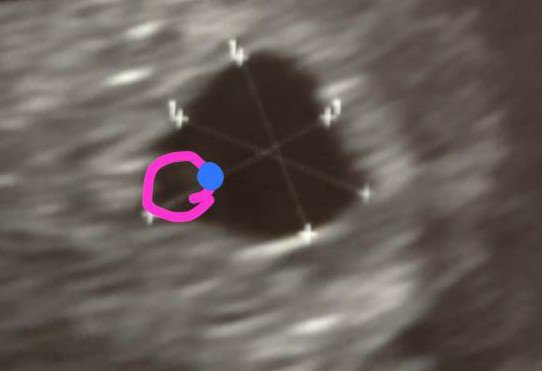

Dziewczyny moja koleżanka która jest specjalistką we wczesnych ciążach mnie troszku pocieszyła i powiedziała że mam woreczek żółtkowy który wygląda jak pierścionek A to bardzo dobry znak więc mam nadzieję. Jutro mam jeszcze jedną wizytę u ginekologa ale raczej nie będę robić USG po prostu chcę L4 do poniedziałku bo psychicznie nie dam rady

Dziewczyny moja koleżanka która jest specjalistką we wczesnych ciążach mnie troszku pocieszyła i powiedziała że mam woreczek żółtkowy który wygląda jak pierścionek A to bardzo dobry znak więc mam nadzieję. Jutro mam jeszcze jedną wizytę u ginekologa ale raczej nie będę robić USG po prostu chcę L4 do poniedziałku bo psychicznie nie dam radyZobacz załącznik 1246383Zobacz załącznik 1246384

Ja też coś widzę zagnieżdżenie w macicy